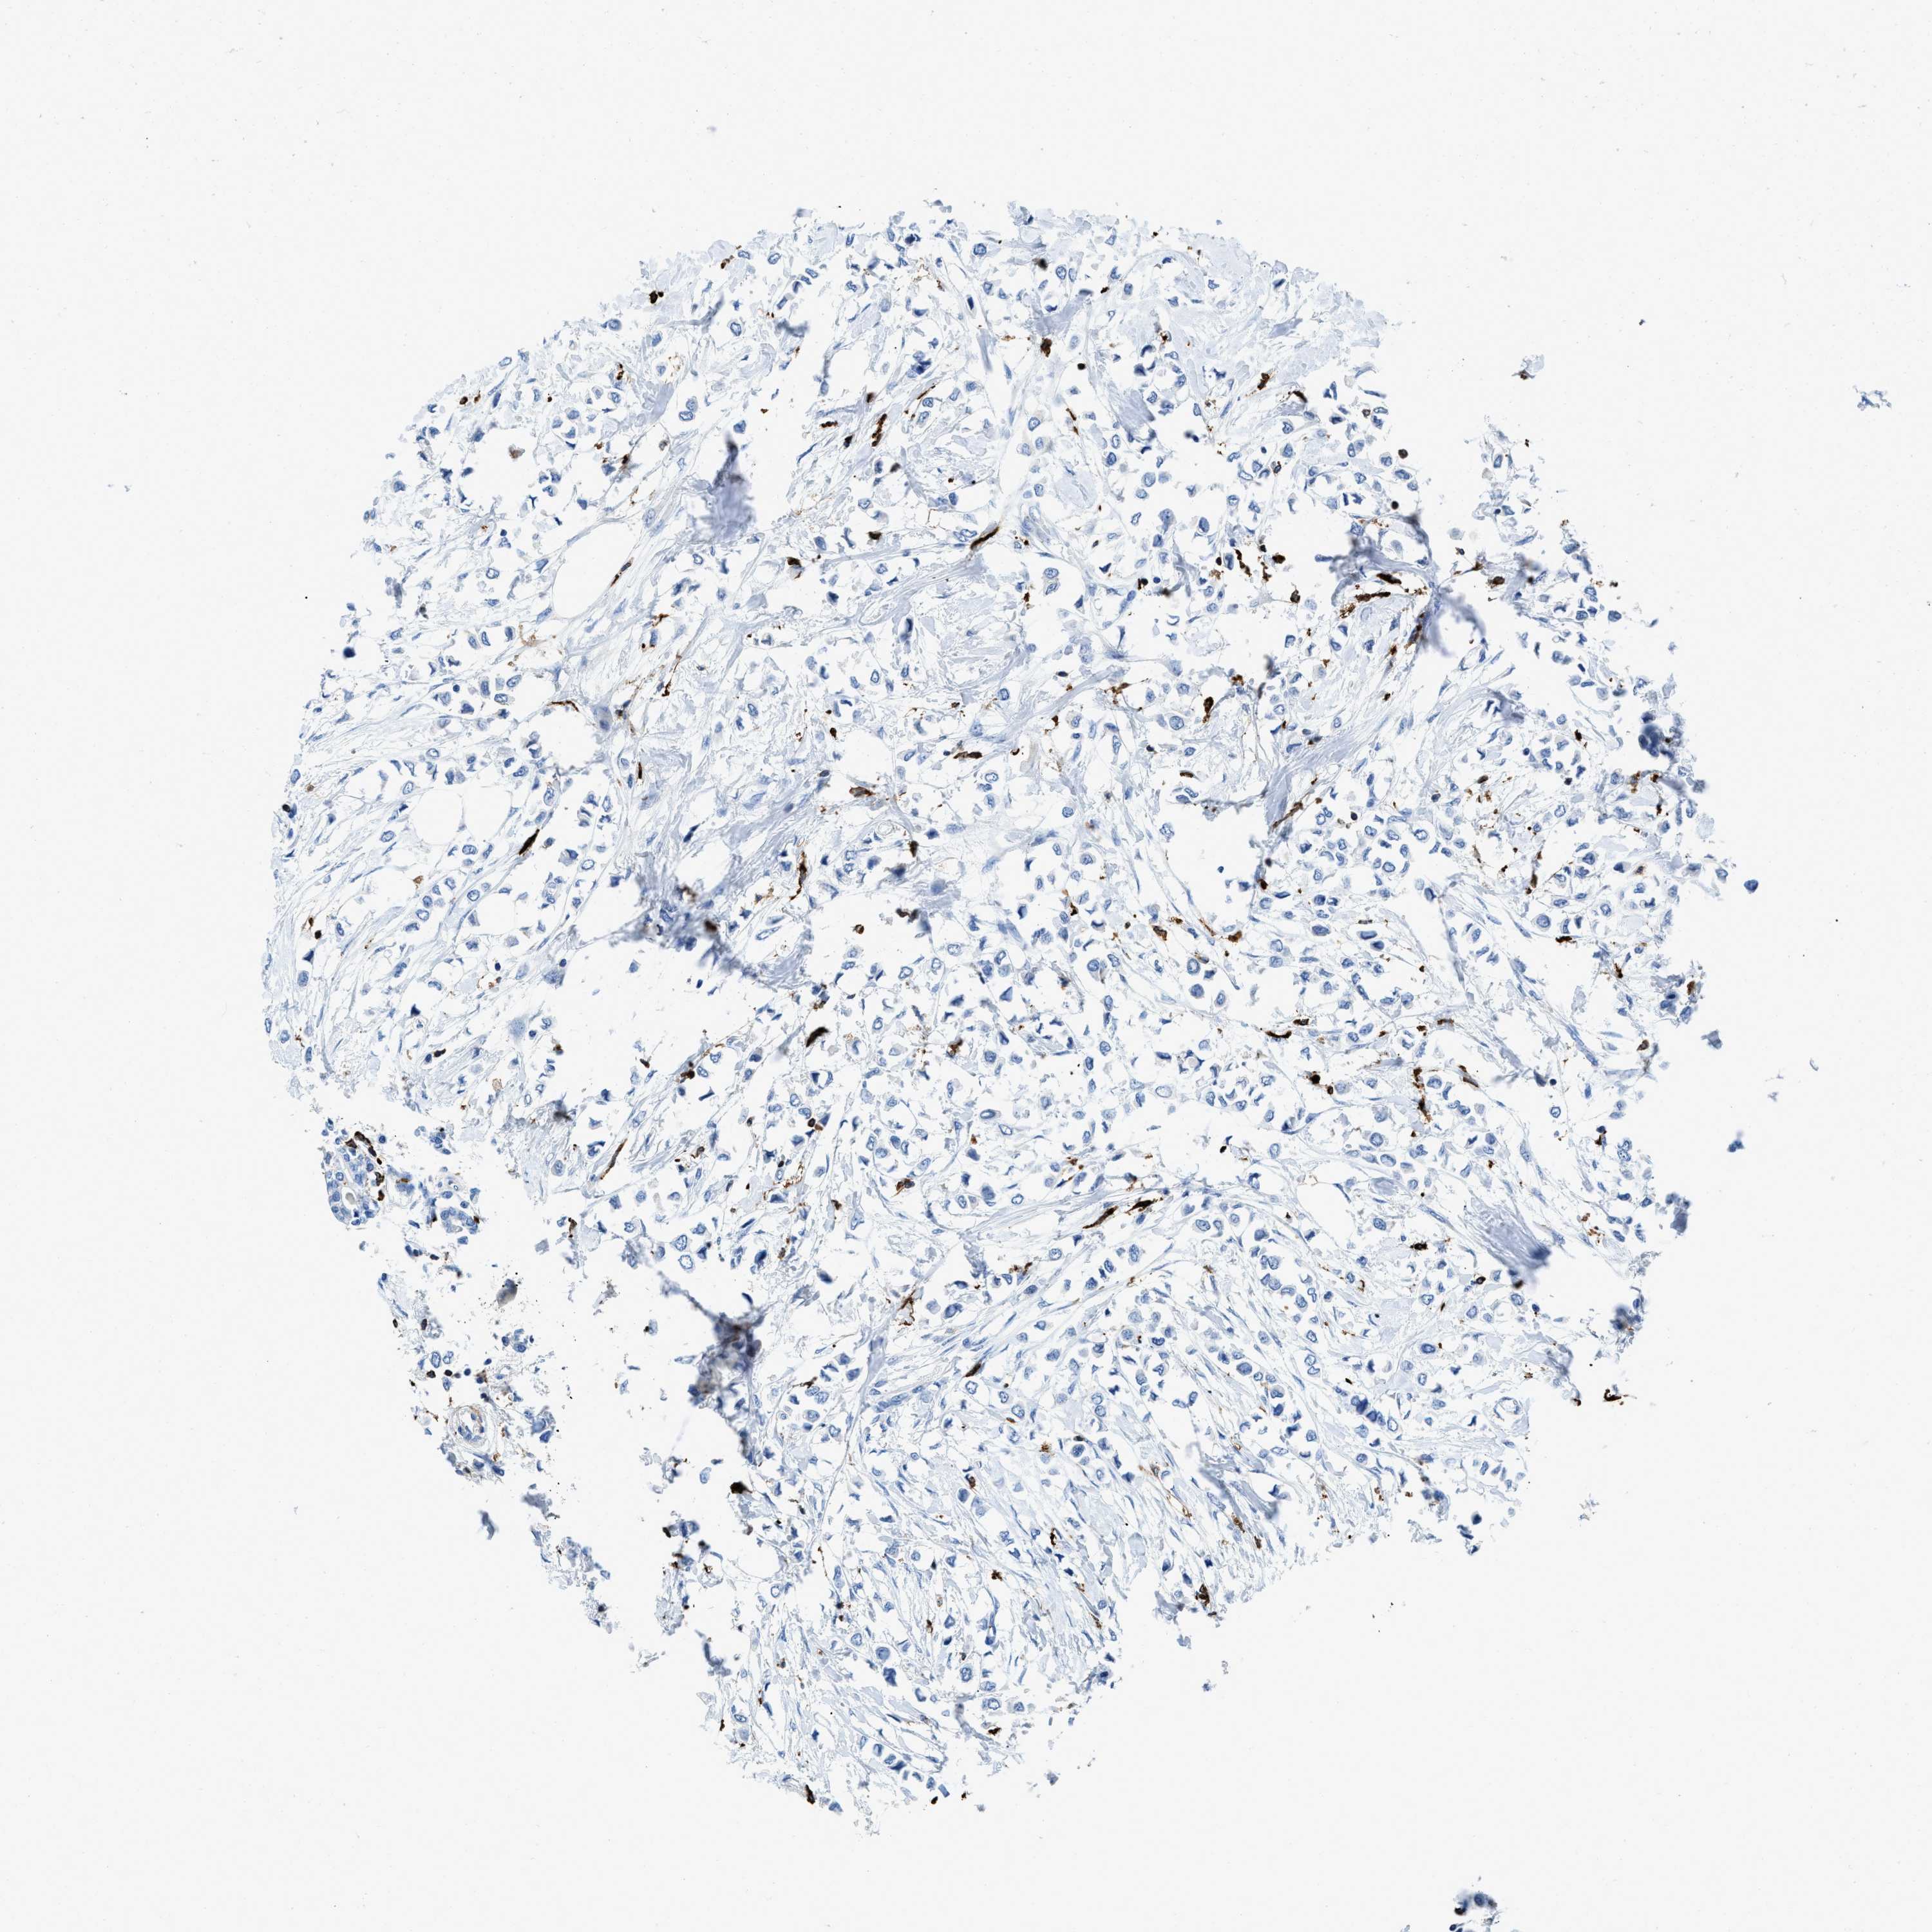

CANCER BREAST CANCER Show tissue menu

BRCA TCGA BRCA VALIDATION PROTEIN EXPRESSION

CD226 is not prognostic in Breast Invasive Carcinoma (TCGA)

Average pTPM 1.3

Number of samples 1022